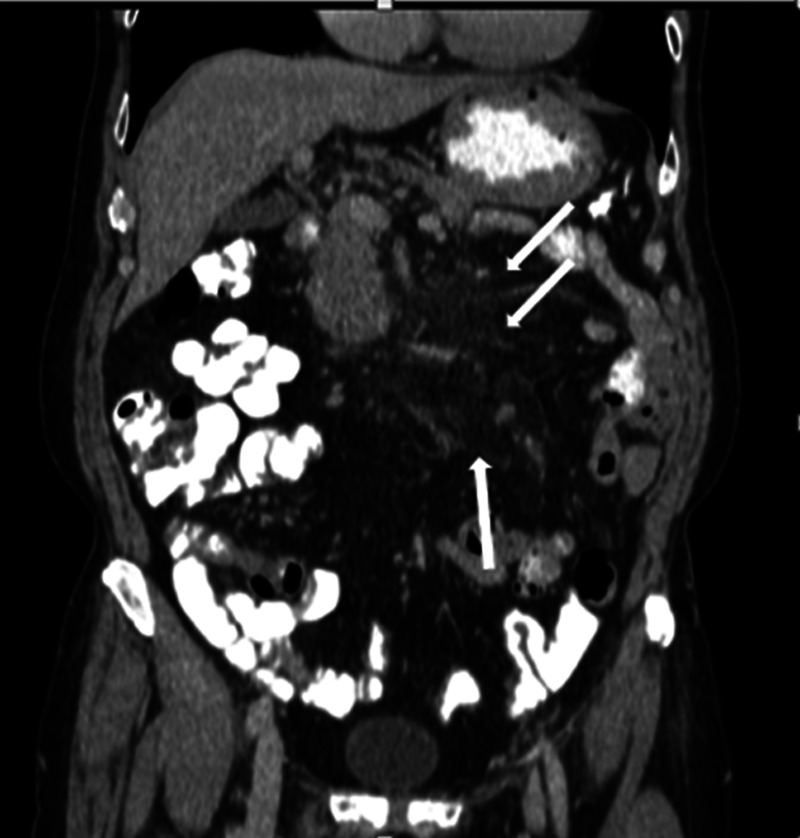

Figure 4.

Coronal contrast-enhanced CT image showing a hyperattenuated fatty mass at the mesenteric root (arrows).